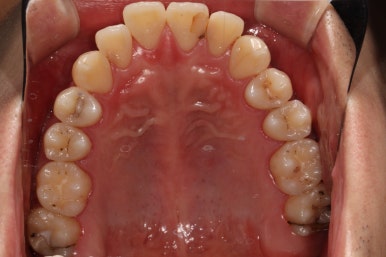

충치가 많은 것 같아요. 치료할 것은 다 치료받고 싶어요.

얼마 전에 저희 병원에 왔던 환자입니다.

어머니는 우리 병원을 오래 다녔던 환자분. 저희 치과를 믿고 방문해 주셨습니다.

충치는 몇 개 일까요?

맞아요. 충치는 대체 몇 개 일까요?

까맣게 보이는건 다 치료해야할까요?

얼마나 어떻게 치료할진 누가 결정하는 걸까요???

저 뿐만 아니라 우리 모두 까만색이 몇 갠지는 셀 수 있으니까,

제가 세보니깐 총 17개였습니다.

그럼 총 치아가 28개인데 17개가 썩었으니... 약 60%정도가 충치라는 얘기네요...